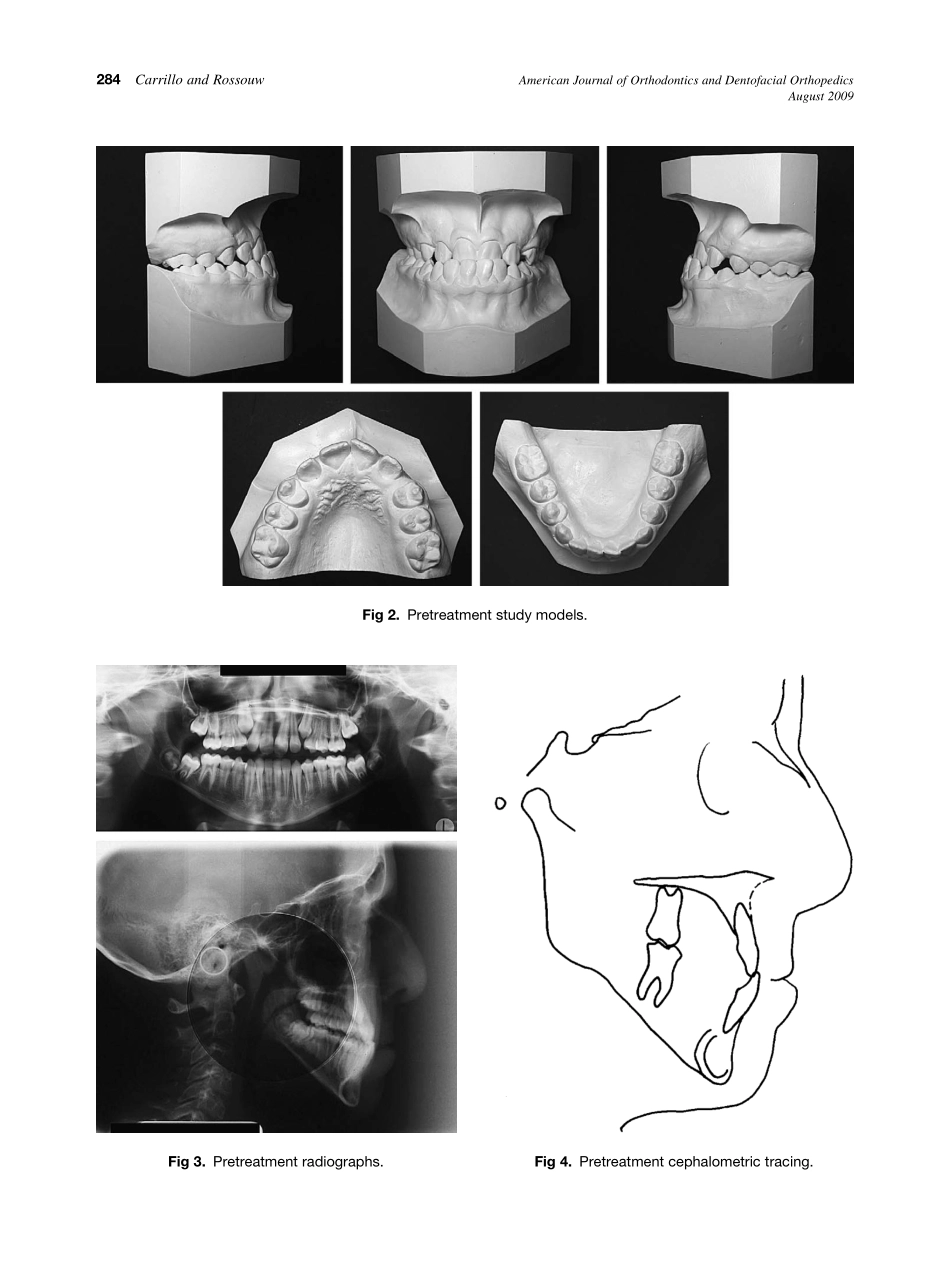

CASEREPORTOrthodontictreatmentforapatientwithcongenitalcutislaxaRobertoCarrilloaandP.EmileRossouwbMonterrey,Mexico,andDallas,TexThiscasereportwasshownatthestudentcasedisplay,sponsoredbytheCollegeof...